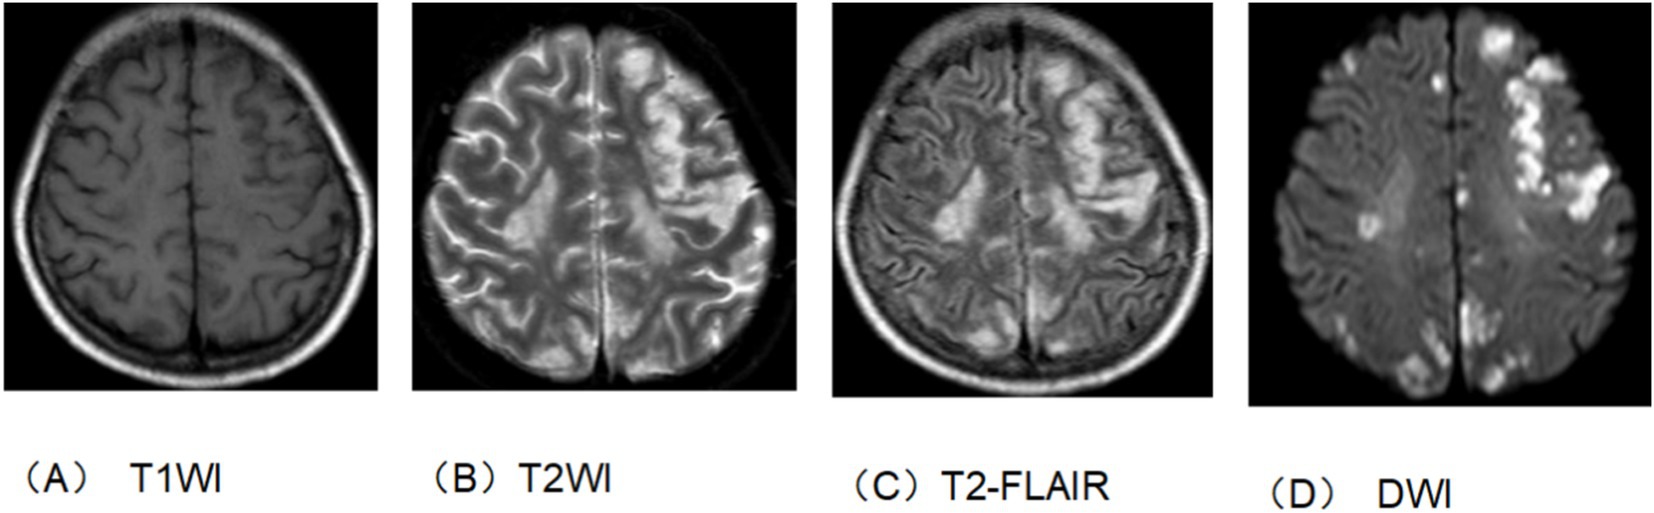

The patient, a 50-year-old woman, was diagnosed with adenocarcinoma of the pancreatic head one year prior and underwent laparoscopic pylorus-preserving pancreaticoduodenectomy. Twenty days before admission, she presented with vomiting. Past medical history: the patient has not had a brain infarction and denies a history of atrial fibrillation or hyperlipidemia. Family history: no family history of tumor, brain infarction, coronary heart disease, etc., and nothing special in the rest. The patient has a physical examination every 3–5 years with no significant abnormal findings. A follow-up abdominal CT suggested tumor recurrence and metastasis near the portal vein main trunk, pancreatic head, and mesentery. She was treated with a chemotherapy regimen including Gemcitabine and albumin-bound paclitaxel. Post-chemotherapy, she developed bleeding, fever, and chills. Laboratory tests revealed anemia, thrombocytopenia, leukopenia, elevated C-reactive protein, and interleukin-6 levels. Blood cultures identified multiple pathogens, and a CT scan indicated a liver abscess (14 × 10 cm), as shown in Figure 1. The patient received various antibiotics and underwent ultrasound-guided liver abscess drainage, yielding over 1,000 mL of pus infected with Escherichia coli. Shortly after, she experienced respiratory distress and was treated with oxygen therapy, methylprednisolone, and aminophylline. She then developed right-side limb weakness and left-upper limb fatigue. A head and neck MRI indicated acute brain infarction, as shown in Figure 2. Due to contraindications for thrombolysis or thrombectomy, she continued to receive anti-infection, diuretic, and mannitol treatment. Her condition worsened, resulting in incontinence, mixed aphasia, and decreased right-side sensation. Despite treatment, her symptoms did not improve, and she was discharged at the family’s request. The timeline of the episode of care is showed in Figure 3.

Figure 2. Head and neck enhanced MRI. (A) T1 sequence. (B) T2 sequence. (C) T2-flair sequence. (D) DWI sequence. The bilateral rated lobes scattered in multiple patchy and nodular slightly longer T1 and long T2 signal shadow. T2-flair showed hypertension and DWI showed high signal intensity. This suggests brain infarction.